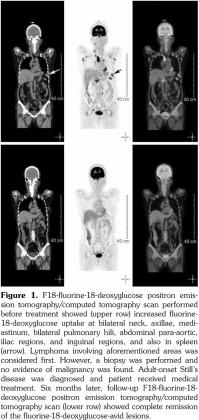

A 53-year-old female patient suffered from pain over most of her body, particularly the joints and the throat. In addition, skin rashes on the trunk without pruritus were noted. She had visited the Rheumatology, Neurology, and Orthopedic Outpatient Department several times. A chest computed tomography (CT) was performed which revealed multiple lymphadenopathies over cervical, mediastinal, and axillary areas. A positron emission tomography (PET)/CT revealed increased fluorine-18-deoxyglucose (FDG) uptake in many lymph nodes including the bilateral neck, axillae, mediastinum, bilateral pulmonary hili, abdominal paraaortic region, iliac regions, and inguinal regions as well as the bone marrow and the spleen (Figure 1). In addition, mild and diffuse increase of FDG uptake in the bone marrow was noted. Lymphoma was suspected first. After discussing with the patient, thoracoscopic mediastinal lymph node biopsy was performed. Fifteen lymph nodes were taken and the results showed histiocytic infiltration in sinusoid area and anthracotic pigment deposition. Reactive lymphoid follicle hyperplasia and focal fibrocalcified nodule formation were also noted. No tumor cell was seen. Gallium-67 (Ga-67) scan was conducted and no gallium-avid tumor was seen throughout the whole body (Figure 2). The laboratory data were negative for antinuclear antibodies, rheumatoid factor- immunoglobulin M, and extractable nuclear antibody, while alanine aminotransferase was high. The final diagnosis was AOSD. In our case, there were no symptoms or signs of either high fever or debilitating joint although the FDG PET showed multiple FDG-avid lesions in the whole body scan. According to the experience of our rheumatologists, methylprednisolone (Metisone) 4 mg/day and non-steroidal anti-inflammatory drugs were prescribed initially and the response to treatment was good. Six months later, the follow- up PET/CT showed complete remission of the FDG-avid lesions seen in the previous PET/CT (Figure 1) and the patient’s symptoms relieved. A written informed consent was obtained from the patient.

In this study, we present the FDG PET/CT and Ga-67 scan findings of a patient who met the Yamaguchi classification criteria for AOSD. The FDG PET/CT scan was not helpful in diagnosing AOSD in this case since lymphoma could not be ruled out. However, the FDG PET/CT scan results were useful for evaluating the distribution and severity of the disease. A negative Ga-67 scan could be beneficial as it would exclude lymphoma. After the diagnosis of AOSD was established, the patient received nonsteroidal anti-inflammatory drugs and glucocorticoids with a good response. Disease activity and therapeutic response were monitored by FDG PET/CT and the findings of a scan performed six months after treatment were negative.(13)

The treatment of AOSD remains largely empirical, relying so far on a few prospective or retrospective studies and not on double- blinded randomized trials with suitable sample sizes.(12) In our case, there were no symptoms or signs of high fever, debilitating joint or life- threatening complications although the FDG PET showed multiple FDG-avid lesions in the whole body scan. According to the experience of our rheumatologists, low dose of corticosteroids was prescribed first and the response to treatment was good. The patient’s symptoms and signs relieved and the follow-up PET/CT showed complete remission of these FDG-avid lesions six months later.